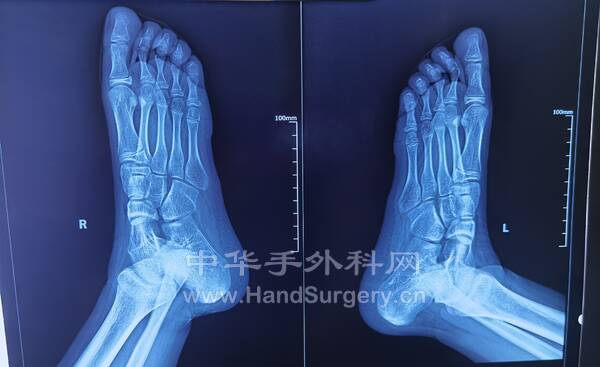

今日得偿所愿,上午跟着老师参观双侧青少年柔韧性扁平足微创扁平足制动器矫正术,双侧副舟骨切除胫后肌腱止点重建术的

13岁男性患者,用的威高扁平足制动器(但大博2代扁平足制动器相对较好)。

副舟骨切除,用直径3.0mm可吸收螺钉固定,与胫后肌腱加固缝合,腱骨缝合,用2.5mm克氏针在舟骨上打孔,放入强生直径3.0mm可吸收铆钉(丝线亦为50%可吸收线),远端与胫后肌腱编织缝合加固!术后6周不能行走。